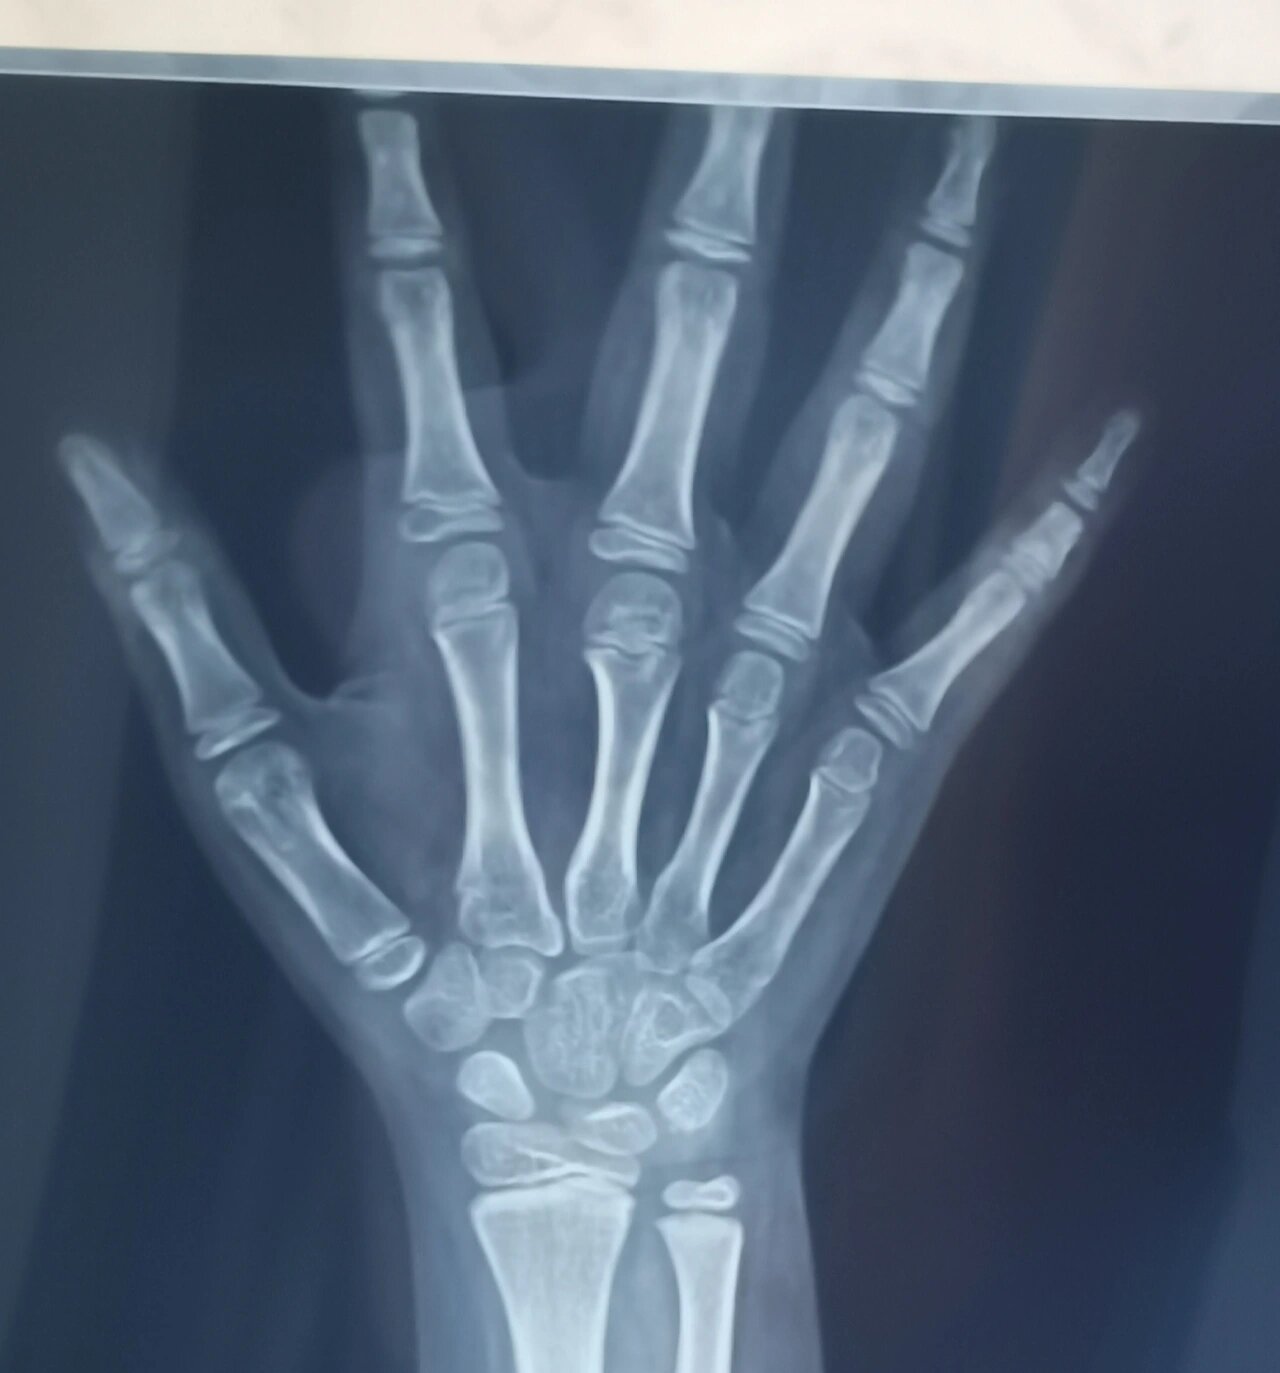

左腕正位显示7个骨化中心,尺桡骨远端骨骺出现,未闭合;双手掌指关节

方法:根据手掌的指骨,腕骨以及桡骨,尺骨下端的骨化中心的发育程度等

医生通过x光片观察左手掌指骨,腕骨及桡尺骨下端的骨化中心的发育程度

通过x光片观察左手掌指骨,腕骨及桡尺骨下端的骨化中心的发育程度,来